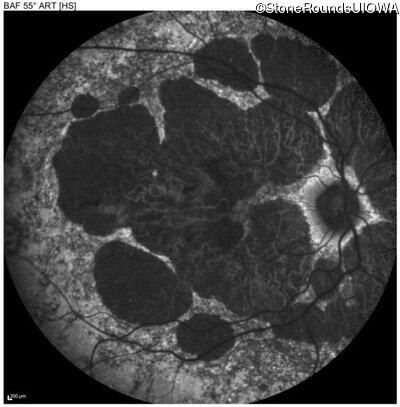

Age at visit: 51 years

OD OS

This 51 year old woman first experienced some abnormality in her distance vision when she was 27 years old. She feels that her vision has been stable since that time.